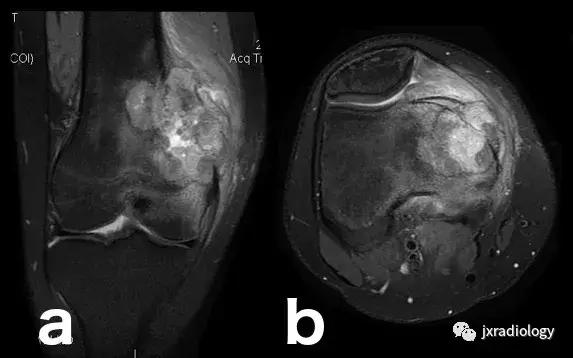

图22:骨肉瘤(a,b:冠状和轴向PD-FS-WI):肿瘤性水肿继发于骨小梁破坏引起的直接毛细血管损伤,并伴有血管内液体释放和出血。 区分周围水肿和肿瘤侵袭可能是困难的。

图23:骨巨细胞瘤(PD-FS-WI):也存在肿瘤性骨髓水肿。